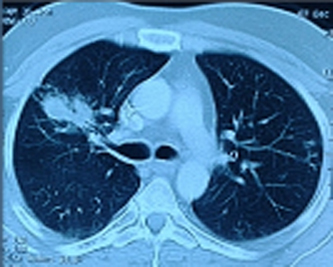

Pneumonia is the infection of the lungs, acquired by inhaling the infecting particles/organisms.